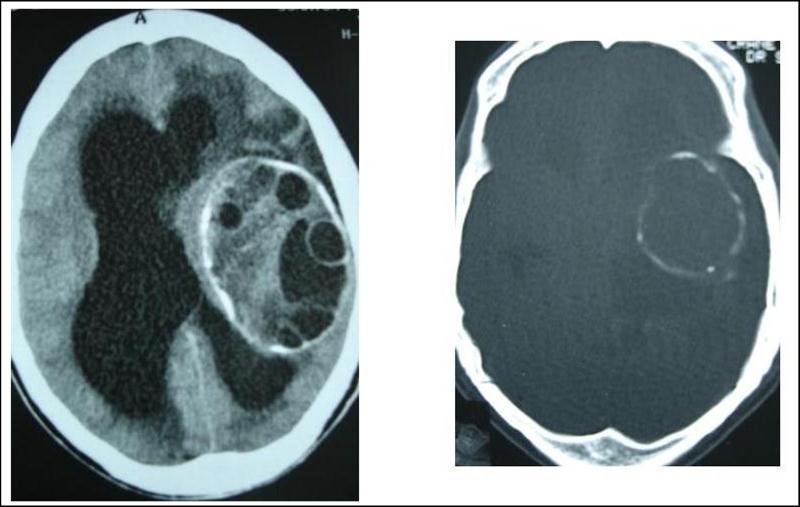

A 27 years-old male patient was admitted with 1 month history of headache, fever, short term memory lack, aphasia, right hemiparesis and seizures. He had liver hydatid cysts excised 8 years before and was treated with adjuvant medication (albendazole). The neurological examination revealed right central third cranial nerve palsy and hemi paresis, with Babinski sign positive, aphasia and papilledema on ocular fundus. The Glasgow Coma Scale was evaluated to 10/15 (E:3; V:1; M:6). A brain CT scan showed a large left temporoparietal intracerebral multiple and calcified hydatid cysts, important mass effect with midline shift about 7 mm following by an obstructive hydrocephalus (Figure 1). Other cysts were found in thalamic region (Figure 2). The Thoraco-abdominal CT scan showed multiple intra peritoneal hydatid cysts (Figure 3). A left temporo parietal craniotomy was performed in emergency. After corticectomy, using Arana-Iniguez technique, the appearance of the capsule suggested infected hydatid cysts with a purulent material which was aspirated. Numerous hydatid cysts were lifted away and several daughter vesicles were carefully removed without rupture (Figure 4). Macroscopically, the abscess wall appeared to be thick, calcified and tightly attached to lateral ventricular, so it could not be removed. The deep cyst overlying the third ventricle was left.in place. Microscopic examination demonstrated live scoleces, protoscoleces and multiple hooks. These findings are consistent with hydatid cyst (granulosis ecchinococcus) (Figure 5). Bacteriology examination found several white blood cells in the pus (neutrophilia) and infection by streptococcus pneumonia. This was consistent with infection. After surgery, the patient had medication (albendazole, specific antibiotherapy and phenobarbital). The inflammation assessment in the blood showed leukocytosis, a high C-reactive protein rate and increased erythrocyte sedimentation rate. Post operative CT scan was performed and showed the residual calcified capsule and decreased ventricular size (Figure 6). Clinical improvement was achieved after treatment. One month after the initial diagnosis, CT scan of the brain showed no recurrence and a physical examination revealed a neurologically intact, fully functional patient and eyes fundus normal. He was discharged and went to abdominal surgery two months later with complete intra abdominal cysts removal. Albendazole treatment was continuing for six months and radiological exploration was performed by brain MRI with spectroscopy at three and six month later. This showed that infection had resolved and the deep cyst overlying the third ventricle is less spherical (Figure 7, Figure 8). Four years later, the outcome was good.

Figure 1.axial CT scans of brain showing multiple hydatid cysts (A) with calcified capsule (B).